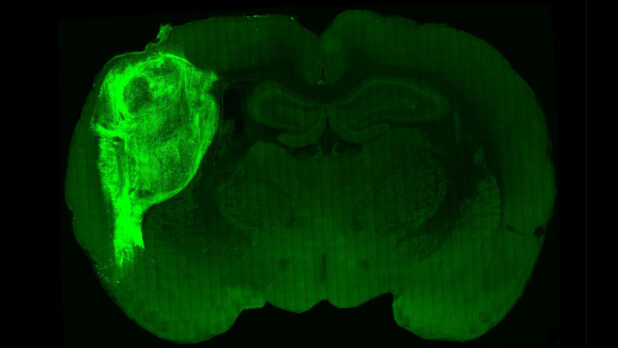

Scientists transplanted those organoids into rat pups 2 to 3 days old, a stage when brain connections are still forming. The organoids grew so that they eventually occupied a third of the hemisphere of the rat’s brain where they were implanted. Neurons from the organoids formed working connections with circuits in the brain.

Bright green: human brain cells.